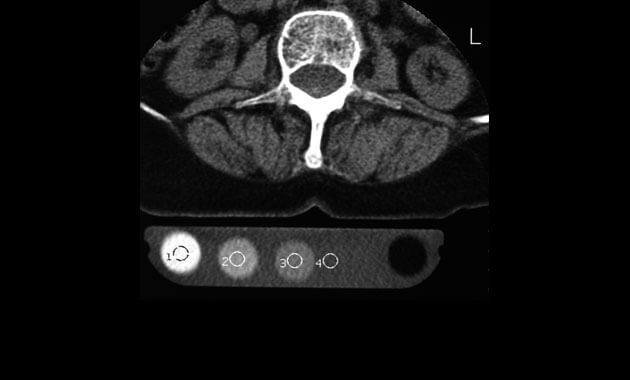

Pioneered at UCSF, quantitative computed tomography (QCT) is a test to measure bone mineral density (BMD). It is performed using a computed tomography (CT) scanner and results in a 3D image. Hip and lumbar spine are the most common choices for evaluation with QCT.